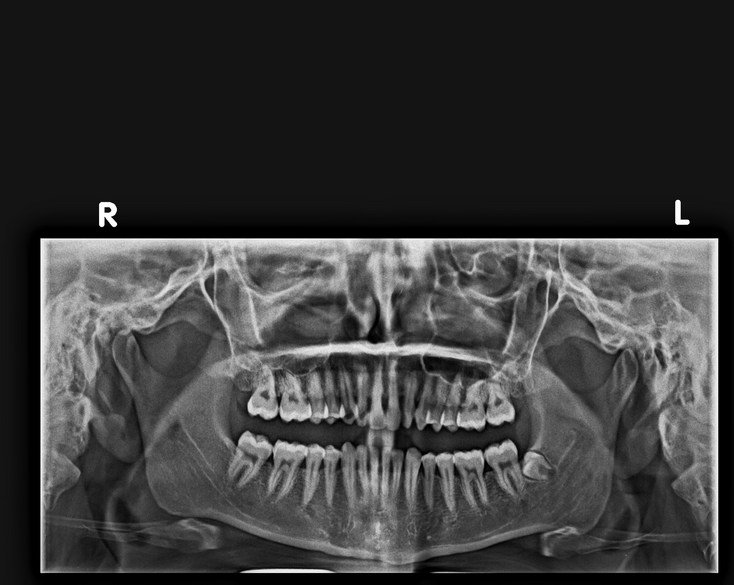

OPG